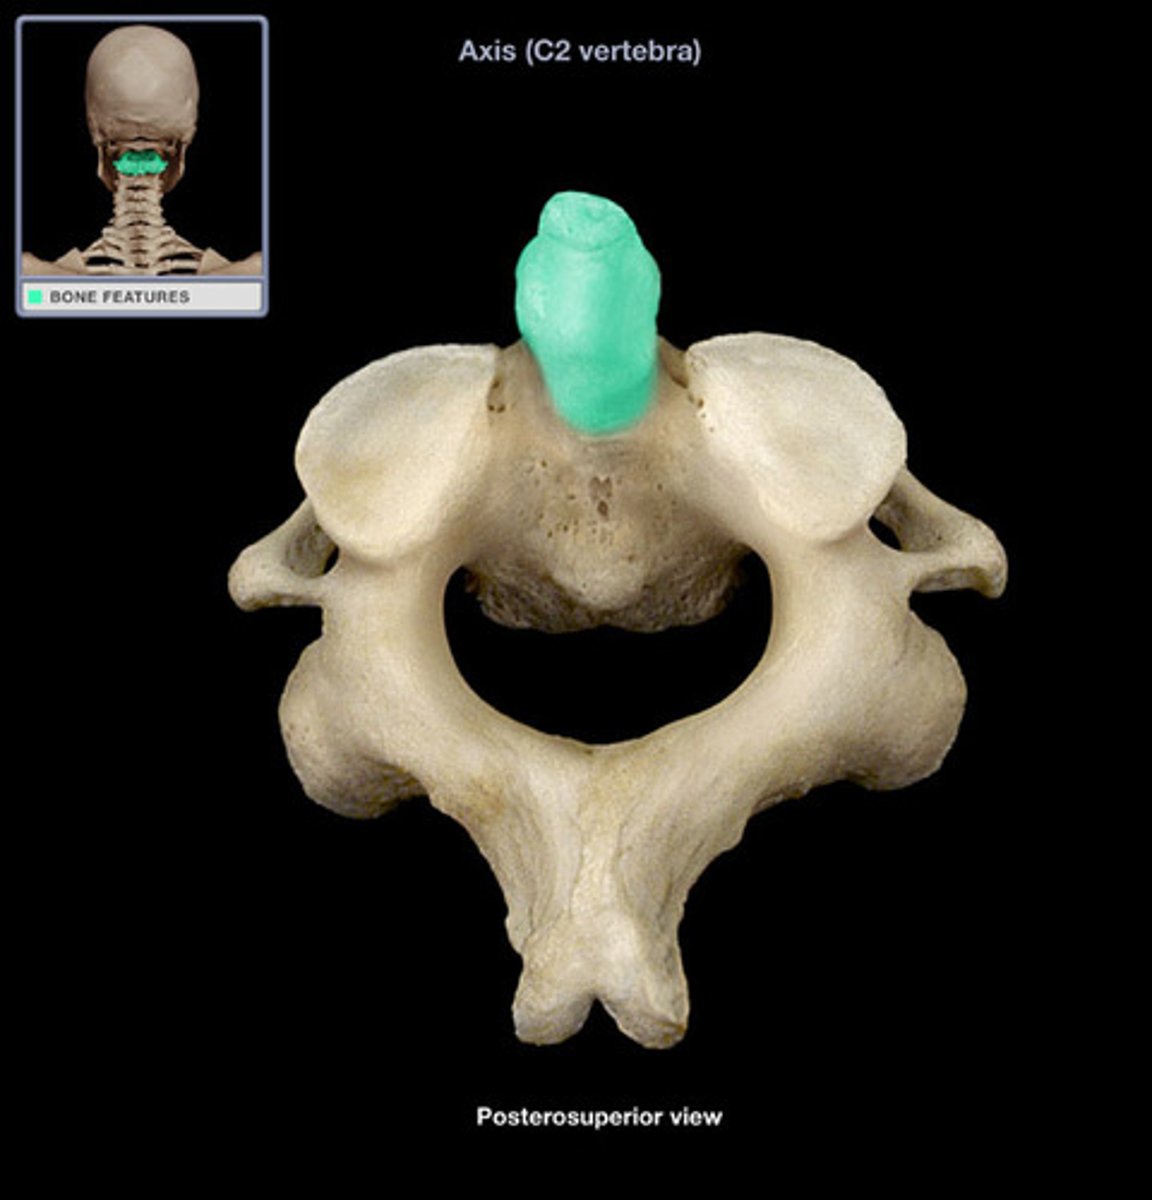

dens (odontid process)

axis C2

C2

what vertebra is considered the axis

allows u to turn head

what is purpose of c2

adontoid process (dens)

what structure allows for head rotation in C2

adontoid process (dens)